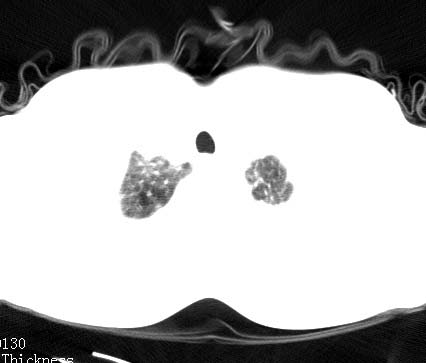

男性 病人 30岁,活动后气促2月余.隔疝伴胸腔积液.右上肺结核!

双肺上结核;膈肌裂孔疝。

左侧胸腔积液,并胸腔内见多个含液 气组织,并相互重叠。影像特征很特殊,应该是“膈疝”。支持!

左侧膈疝,及左侧胸水,双上肺结核。

支持!左侧膈疝,左侧胸水,双上肺结核。